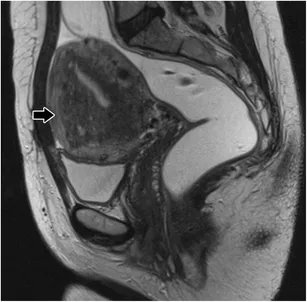

| 40-45 years | Adenomyosis | Painful, heavy | MRI, endometrial biopsy | 75% identifiable |

| >45 years | Perimenopause, cancer | Irregular timing | Endometrial sampling | 70% organic |

Transvaginal ultrasound serves as the primary imaging modality for structural evaluation, providing real-time assessment of uterine architecture and ovarian morphology with 85-90% sensitivity for detecting abnormalities.

Specialized Imaging Indications

Endometrial sampling provides definitive histologic diagnosis when imaging suggests endometrial pathology or clinical risk factors warrant tissue evaluation.